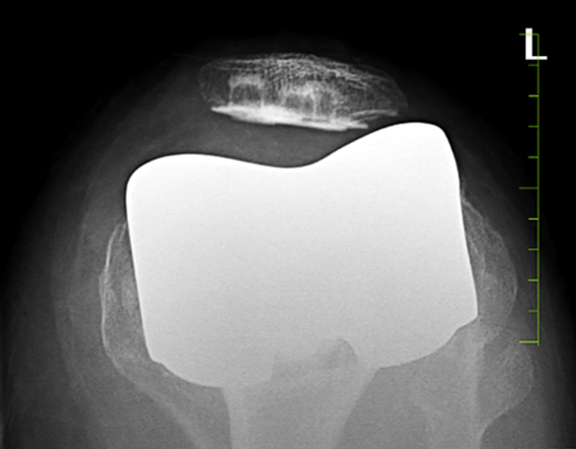

Valgus knees involve surgical challenges to achieve alignment and soft tissue balancing throughout the ROM – flexion, extension, and mid-flexion [10,13]. RA-TKA has developed a new era of real-time balancing, precise component positioning, and yields an advantage in such challenging valgus knees. The inherent accuracy of the CT-based robotic system aids to achieve optimum gap balance. The pre-operative planning (J planner in CT-based CUVIS system in our cohort) delivers an important aspect to plan the placement of femoral and tibial components. Intra-operative adjustments were made for gap balancing, which incorporated the principles of FA. Gap-balancing in the CUVIS robotic system requires anticipation of opening in the compartment after the planned bony cuts. During intra-operative gap balancing, if the opening in the medial or lateral compartment is more than 1 mm on giving a valgus or varus stretch, then chances of an increased gap are more after the bony cuts. After giving a neutral or varus stretch in a valgus knee, if the knee reverts back into valgus spontaneously, then it denotes that the lateral structures are tight; hence, additional release after the bony cuts can be commenced. However, the amount of release required for gap balancing throughout the ROM was comparatively less in RA-TKA cohort with the FA setup. When considering the optimal alignment, the relationship between the prosthesis and the soft tissue envelope may be more important than neutral mechanical alignment [14]. The CPAK classification makes us to calculate the pre-operative MPTA. One can also judge the extra-articular tibia-valga morphology during pre-operative planning, as it is commonly associated with valgus knee deformity. The authors believed that, while we aim to regain the same CPAK phenotype of the knee, MPTA is the most important factor to consider specifically in tibia-valga morphology. The tibia cut was kept in valgus in cases of extra-articular tibia-valga and otherwise neutral or varus in the absence of tibia-valga, which counters medial compartment laxity. Important factor to note- in cases of extra-articular tibia-valga, if the tibia cut is kept in neutral or even varus, this might necessitate increased internal rotation of the femoral component, which may balance the mediolateral gaps but leads to patellar instability. The overall alignment was kept within the “safe zone” up to 3° of valgus in the RA-TKA cohort. Excessive valgus not more than 3° was to avoid erratic component positioning and recurrence of valgus deformity. FA is based on a blend of inherent bony anatomy and an evaluation of soft-tissue laxity [10,15,16,17]. In the RA-TKA cohort, overall limb alignment was targeted within neutral to 3° valgus in the coronal plane based on the arithmetic HKA or pre-operative knee phenotype according to CPAK classification. Multiple studies have been conducted based on FA philosophy using a CT-based robotic platform in the varus knee [15,16]. However, these studies lack application of FA in patients with valgus deformity. Oussedik et al., studied the FA suggested overall limb alignment to be kept within the 0° ± 3° “safe zone” of coronal alignment, and also highlighted on possibility of change in the zones with further research [10]. In the study done by Clark et al, overall limb alignment of between 3° valgus and 6° varus was kept as the safe zone [17]. The role of femoral component rotation plays an important role in case of valgus knee with lateral compartment bony deficiencies and estimation of epicondylar axis is critical. Even in experienced hands, clinical estimation of the epicondylar axis is inaccurate and should not be relied upon as the sole determinant of femoral rotation [18]. Wherein the CT-based CUVIS system is able to estimate the exact surgical epicondylar axis using J planner. As we followed FA in the RA-TKA cohort, the femoral component was rotated internally (to surgical epicondylar axis) up to 2° in 6 cases after a tibial component valgus of up to 2° to achieve equal mediolateral gaps in flexion and extension. The optimum soft tissue tension was achieved in all compartments with good patellar tracking. All 6 patients underwent an additional skyline view X-ray and CT scan at 3-month follow-up to evaluate patella tilt (Fig. 3). However, among those, a single patient revealed increased lateral tilt on skyline view X-ray at 3-month follow-up (Fig. 4).

Figure 3: Post-operative computed tomography knee of a patient who received internal rotation in femoral component internally to 2° with reference to surgical epicondylar axis and equivalent valgus rotation of the tibia component.